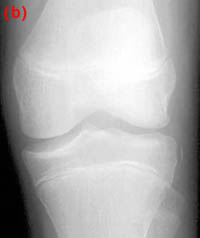

25) Name the abnormality shown in the image below.

26) How can a patellar fracture be distinguished from bipartite or multipartite patella?

27) A patient is known to have a torn ACL and presents for x-ray examination of the knee. Which of the following findings is often associated with a torn ACL?